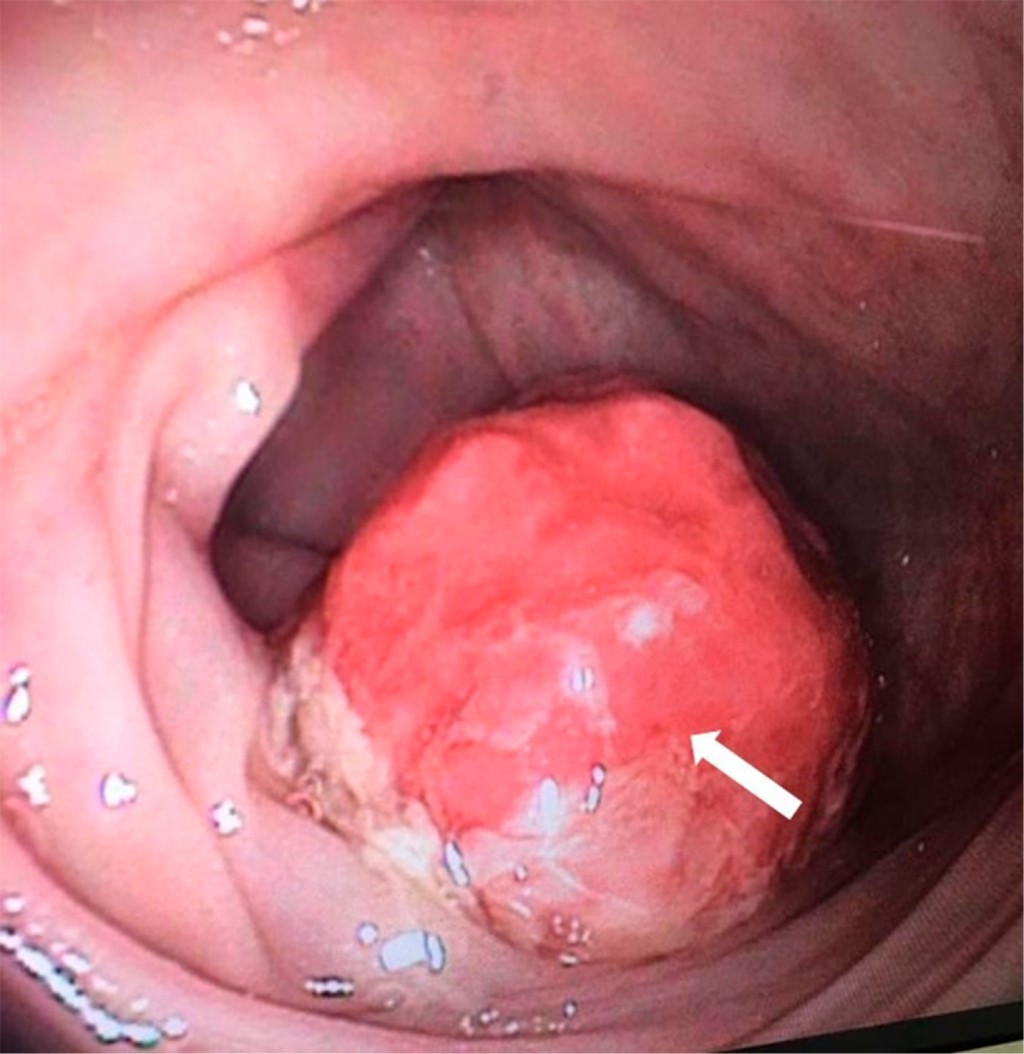

Dos semanas posteriores se realizó colonoscopía total bajo sedación. En el colon sigmoides se encontró un pólipo pediculado gigante de 4 × 2 cm de diámetro, ocupando más de 50% de la luz intestinal (Figura 2). Se procede a enlazar con asa de polipectomía número 20; con coagulación y corte se desprende del pedículo, el cual se recupera y se extrae con canastilla. La paciente no presentó complicaciones durante ni posterior a la polipectomía.

Figura 2